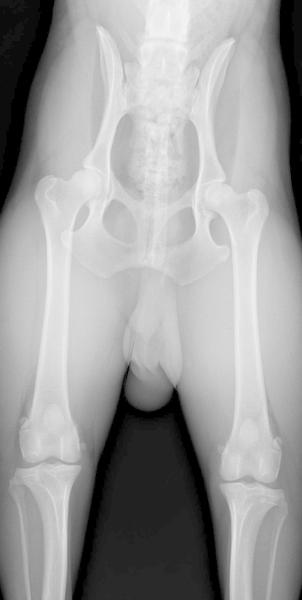

OFA Patellas

PS-PA33/71M/P-PI

OFA Hips

Good

#PS-30G25M-PI